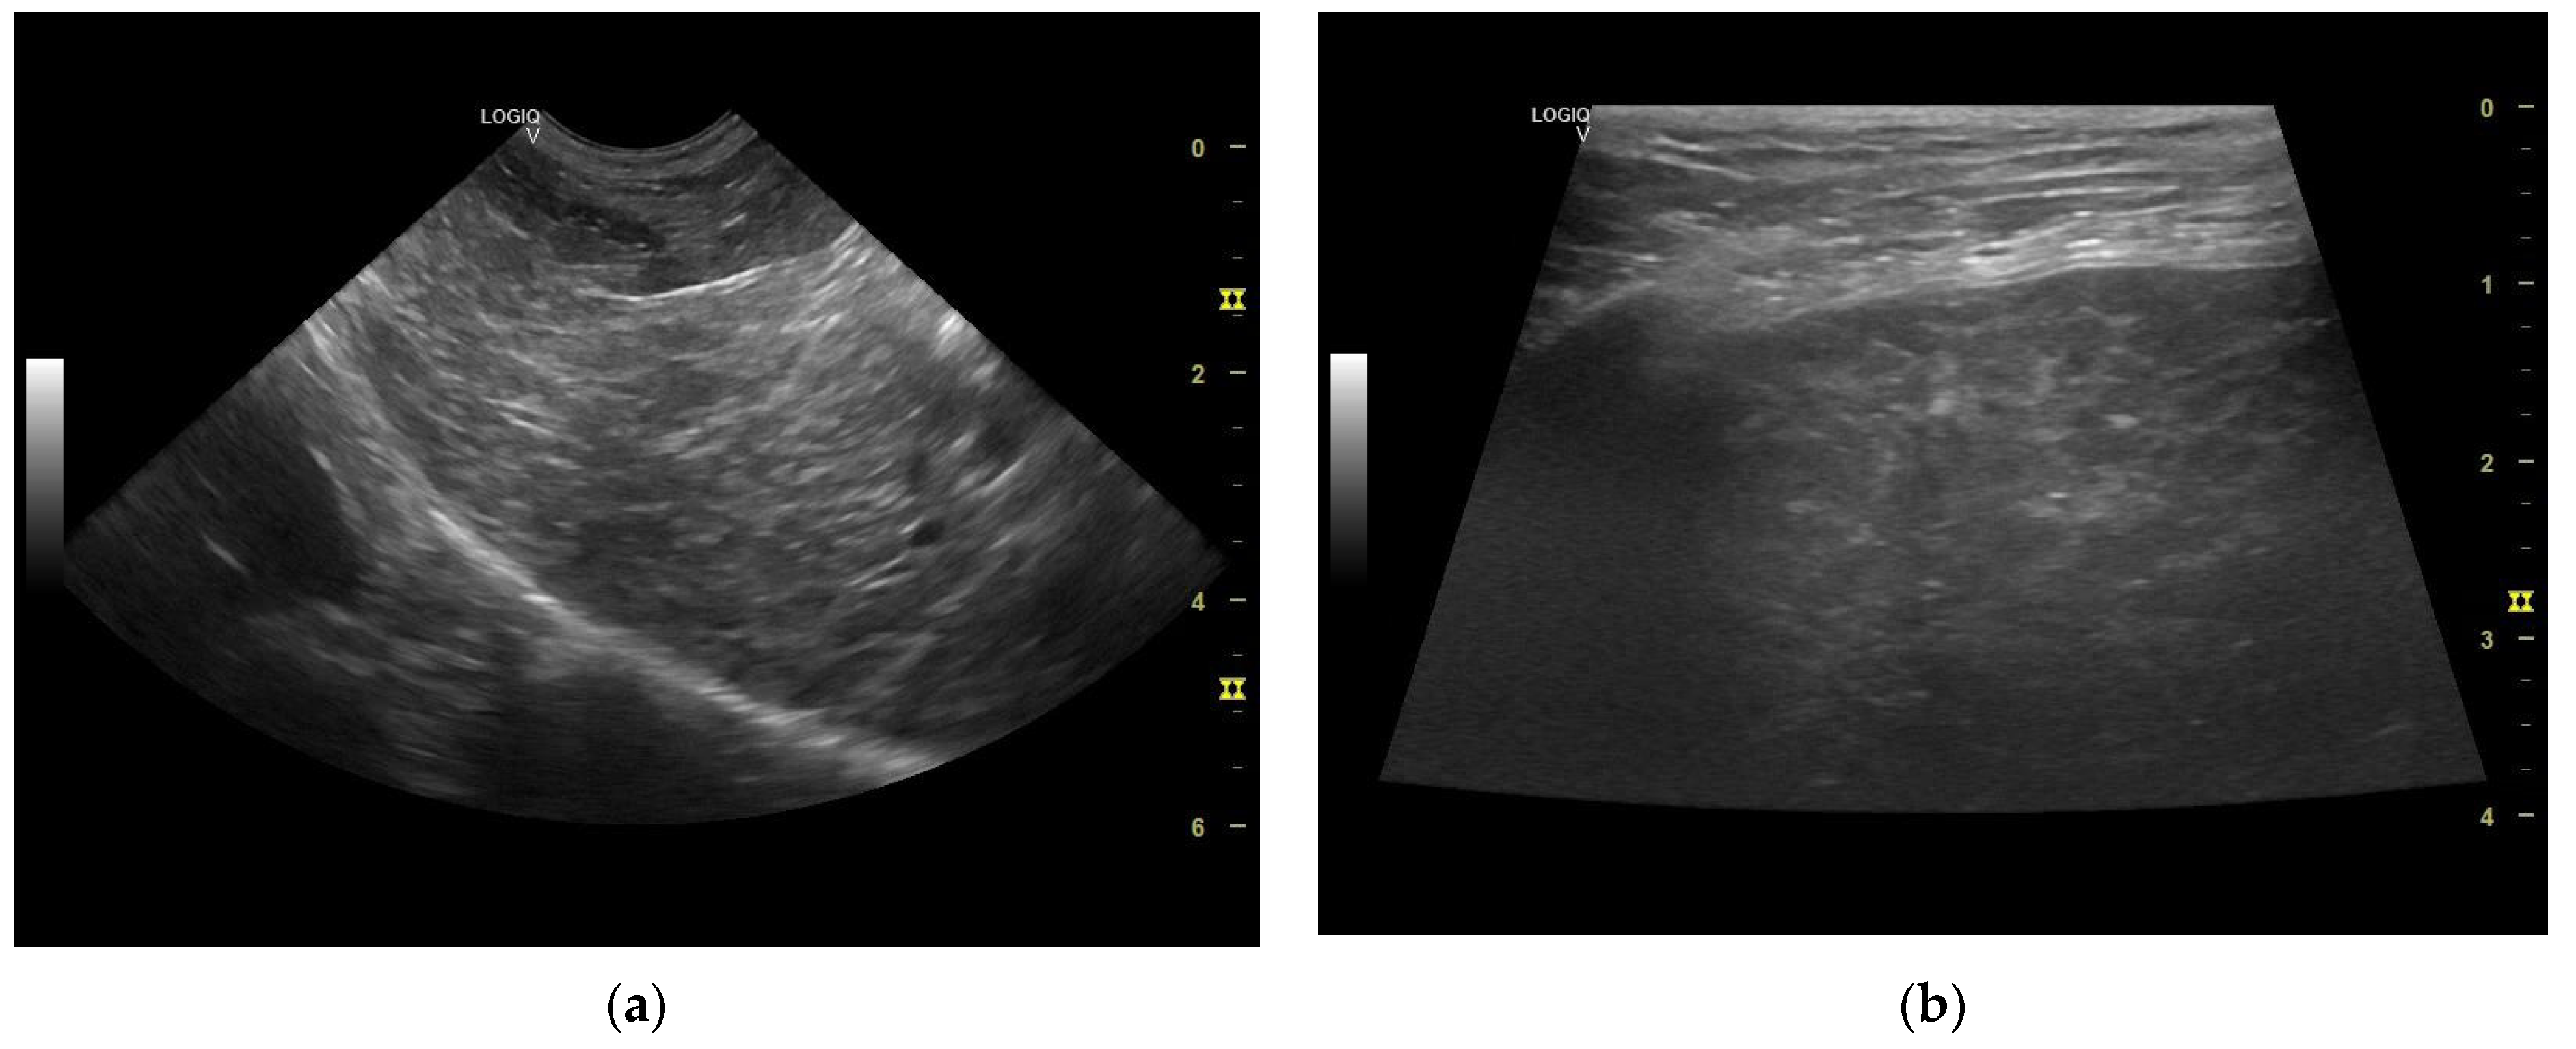

The liver appeared of normal size with non-homogeneous parenchyma, with multiple hyperechogenic strands diffusely dispersed throughout the parenchyma giving it a “Swiss cheese” appearance, with a slightly irregular outline and poorly distinguishable vascular walls (Figure 6 and Figure 7a,b). The gall bladder had a fine hyperechoic wall with anechoic content accompanied by hypoechoic, mobile, gravitationally dependent sediment in reduced quantity.

Figure 7. (a) Liver—non-homogeneous parenchyma (microconvex transducer). (b) Liver multiple hyperechogenic strands diffusely dispersed throughout the parenchyma—“Swiss cheese” appearance (linear transducer).

The ultrasonographical aspect of the liver as well as the normal size of the organ combined with the Swiss cheese-like appearance of the parenchyma corroborates the diagnosis of hepatocutaneous syndrome. Another differential diagnosis in absence of the dermatological findings could have been that of chronic hepatitis/liver cirrhosis, although the liver is reported to be reduced in size in these common conditions.